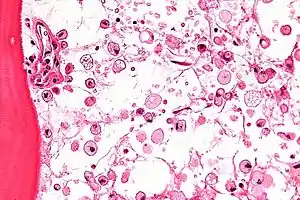

![]() На мікрофотографії відображені характерні зміни будови кісткового мозку при хворобі Гоше — цитоплазма макрофагів нагадує зім'ятий цигарковий папір. Фарбування гематоксиліном-еозином. На мікрофотографії відображені характерні зміни будови кісткового мозку при хворобі Гоше — цитоплазма макрофагів нагадує зім'ятий цигарковий папір. Фарбування гематоксиліном-еозином. | |